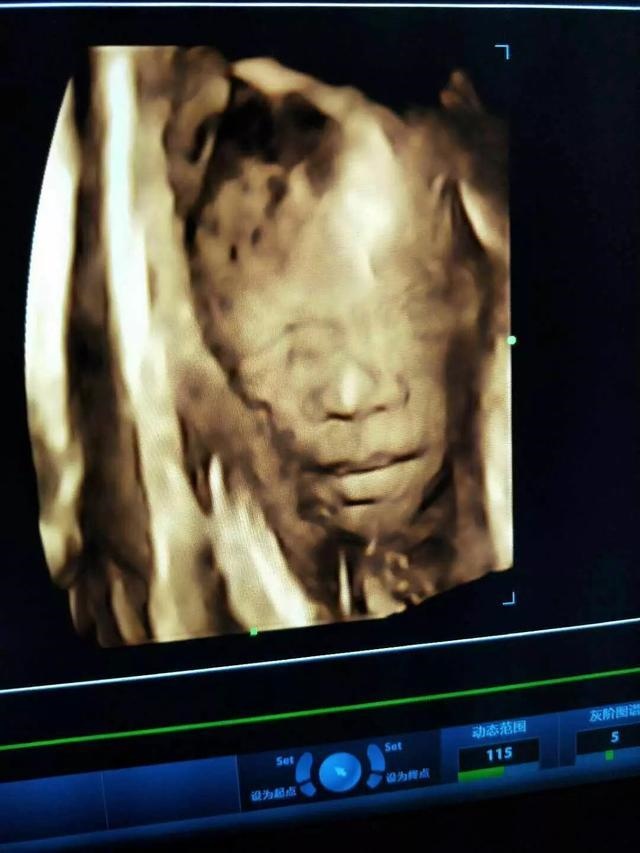

准确率100的生男生女公式准吗,最准确的鉴别男孩女孩

准确率100的生男生女公式准吗1、孕囊数据形状可知晓宝宝是男是女 GS —胎囊也叫孕囊。...